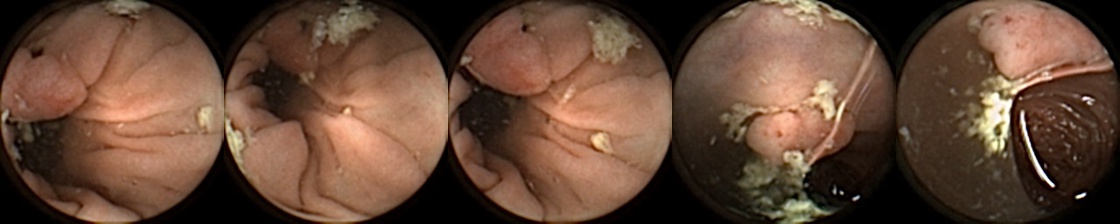

Figure 3 shows classification output examples for the MIV model using the pretrained ConvNext. Note that the model has a test accuracy of 83.66% for DBA L2 with 2 heads. In each row, the leftmost image is the query and the four images to the right of each query are the target images. The True Positive (left-top) and True Negative (bottom-right) examples outline the cases when the model is able to successfully distinguishes images containing unique polyps from those with dissimilar polyps. The False Negative (top-right) and False Positive (bottom-left) examples show the cases where the model fails to correctly distinguish images of unique polyps and images of dissimilar polyps. Further, we can note from the differences in the examples of True Positives and False Negatives that when the query image and the target set instances differ from each other in some ways, then the model can misclassify images. These differences could be attributed to different views due to the dynamics of the camera inside the colon, different views from two camera heads of the capsule, or presence of artifacts such as bubbles, debris, and small bowel secretions.

On the other hand, when we look at the examples of False Positives (Pred = true, Label = false) in Figure 3, we can note that if images in the target match the query in ways such as texture, color, illumination conditions, presence of artifacts, then this may lead to misidentification of the query as belonging to the targets. For True Negative (Pred = false, Label = false) examples, we can see that presence of significant differences between the query and the targets leads to correct identification of the image sets as different.

True Positive False Negative

False Positive True Negative

Figure 3: True Positives (Pred = true, Label = true), False Negatives (Pred = false, Label = true), False Positives (Pred = true, Label = false), True Negatives (Pred = false, Label = false) for the DBA L2(h=2) model using the pretrained ConvNeXt. In each row, the leftmost image is the query and the 4 images to the right of each query are the target images.